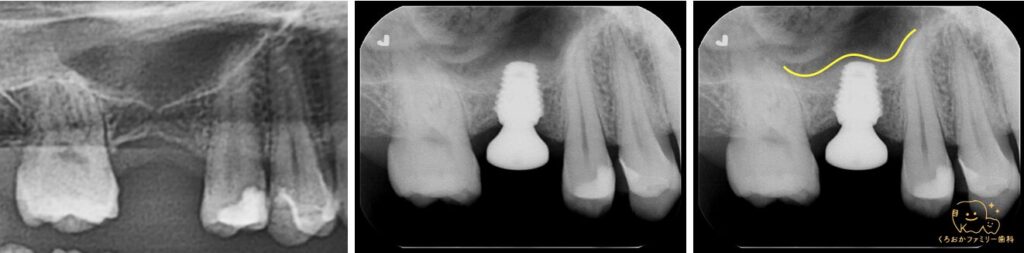

シュナイダー膜を挙上し、骨に穴を開ける際の削片をそのまま持ち上がった空間に入れることで骨ができたかのように見えています。

約3mmという薄い骨に対してもしっかりと固定を取るように埋入できたため一回法での処置が可能となりました。